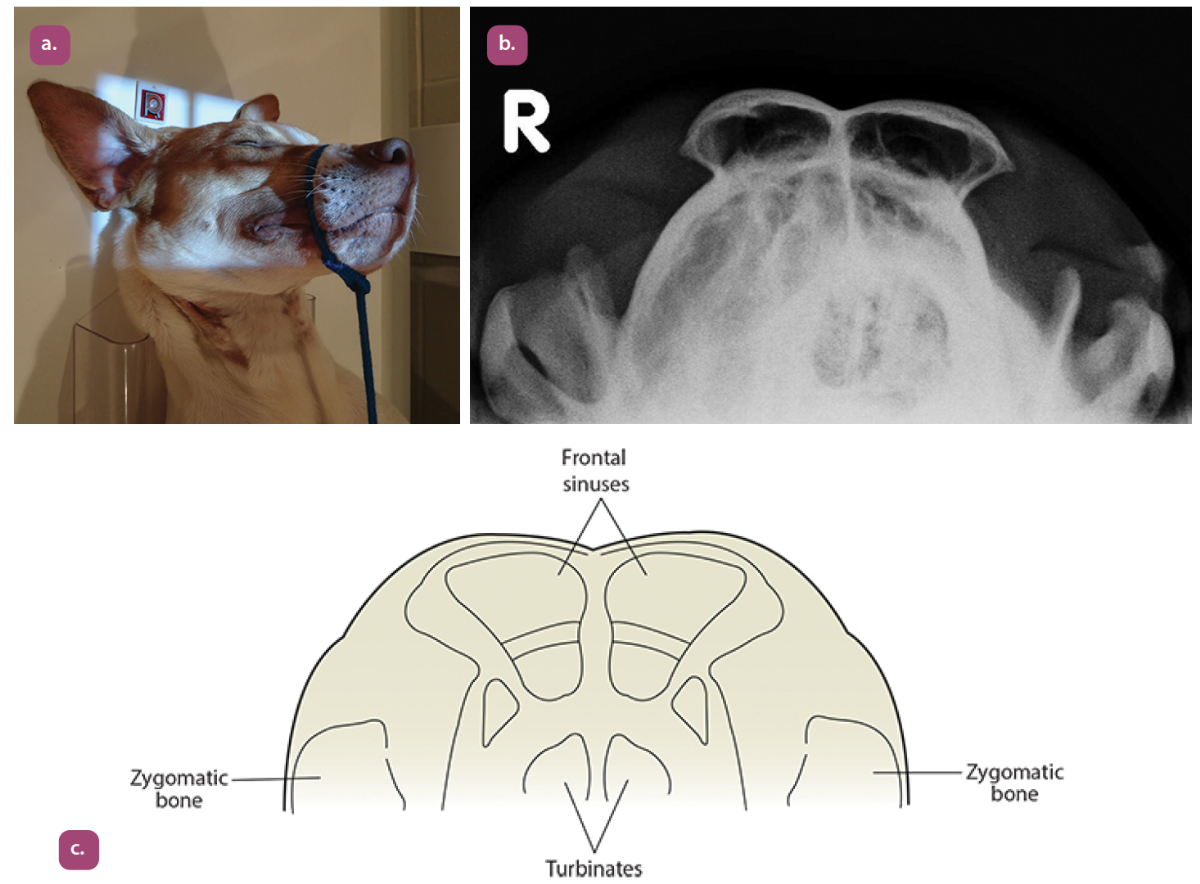

rostrocaudal sinuses closed mouth projection